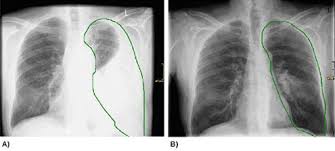

Rontgen Thorax Lunge Grunde Ablauf Bilder Praktischarzt

Kardiologische Rontgenuntersuchung Kleintierspezialisten